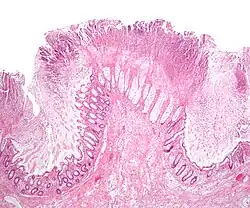

| Micrograph of pseudomembranous colitis, a cause of toxic megacolon. H&E stain. | |

Toxic megacolon is usually a complication of inflammatory bowel disease, such as ulcerative colitis and, more rarely, Crohn's disease, and of some infections of the colon, including Clostridioides difficile infections, which have led to pseudomembranous colitis. Other forms of megacolon exist and can be congenital (present since birth, such as Hirschsprung's disease). It can also be caused by Entamoeba histolytica and Shigella. It may also be caused by the use of loperamide.